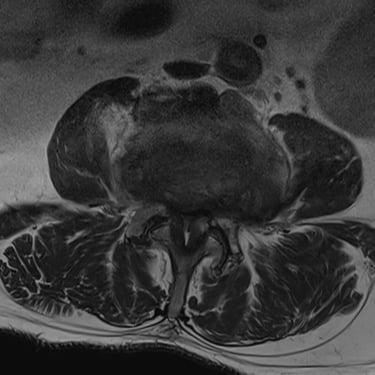

🧠 Tumor Raquídeo Lumbar | Laminectomía y Exéresis de Tumor.

El tumor raquídeo lumbar se manifiesta con dolor, ciática y déficit neurológico. Su tratamiento es la laminectomía con exéresis tumoral, técnica que abre el canal raquídeo para resecar la lesión y descomprimir nervios. El objetivo es restaurar la función neurológica y lograr una recuperación satisfactoria.